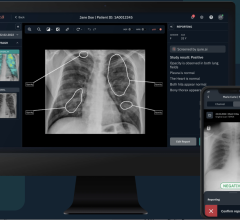

June 18, 2024 — The advancement of Artificial Intelligence (AI) in healthcare to support diagnostic decision making ...

Having the most efficient clinical workflows with enhanced diagnostic capabilities is a major goal for clinicians and ...

Clinicians and referring physicians need fast, secure access to both patient data and their diagnostic or viewing tool ...